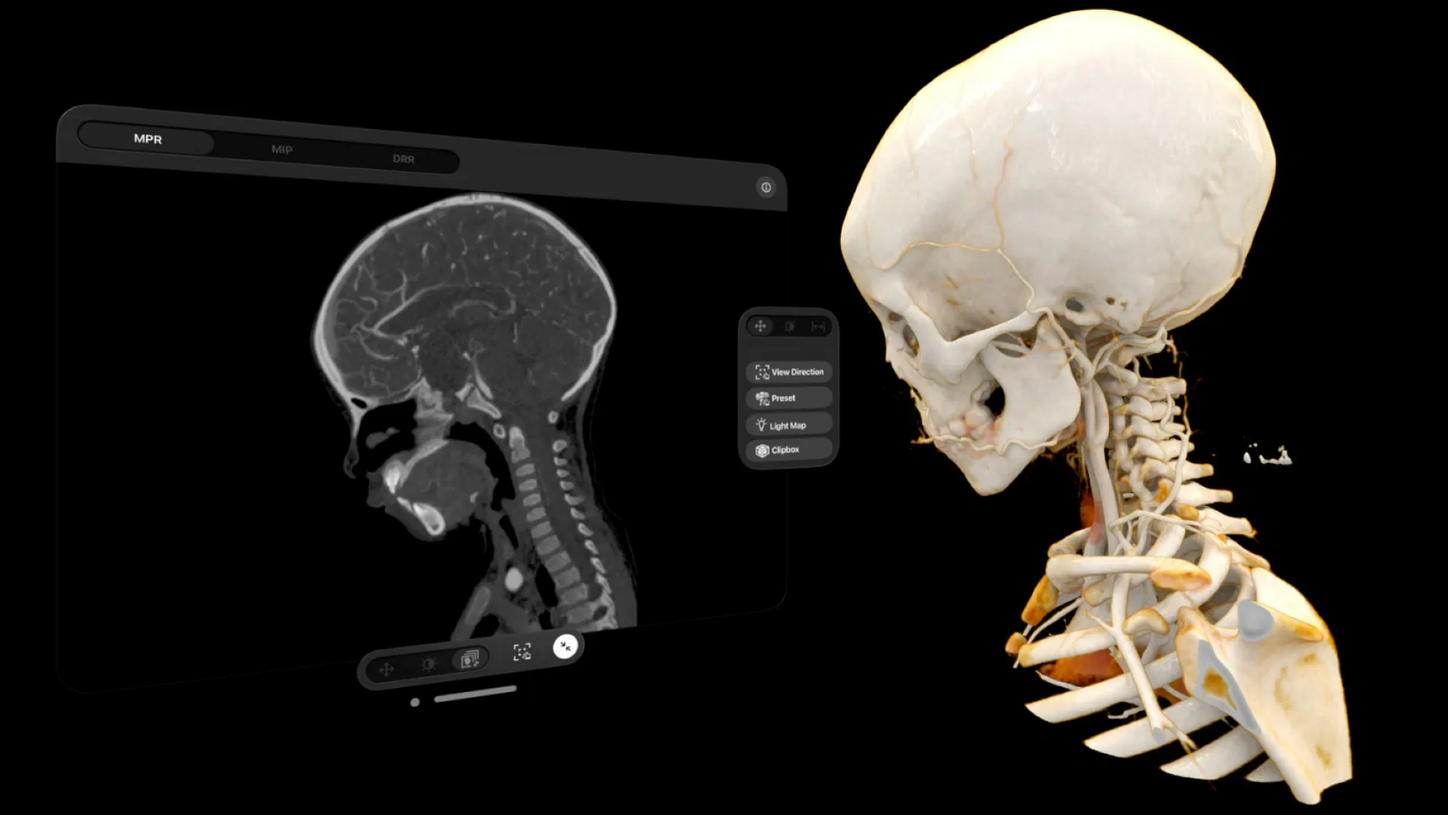

We are empowering decision making for technologists, radiologists, and clinicians along the whole imaging value chain and making it even smarter – allowing healthcare professionals to make the right decision at the right time within the patient pathway. Our AI-powered solutions are not just tools but essential allies in the modern medical imaging landscape, designed to increase productivity, improve clinical precision, and be integrated seamlessly.

Along the imaging pathway there are plenty of levers for productivity and clinical precision

Use seamlessly integrated intelligence to acquire the best images and accelerate your decision making and reporting process through the smart use of data and AI technology. Explore each step within the smart imaging value chain to learn more about our AI portfolio in radiology.